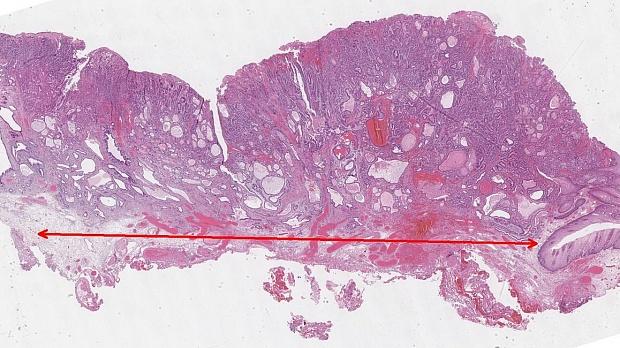

Иллюстрация №10: Рис. 10. Аденокарцинома пищеводно-желудочного перехода. Окраска Гематоксилин-Эозином, увеличение х 100. Инвазивные криброзные очаги аденокарциномы.

Морфологическое и иммуногистохимическое заключение: умеренно дифференцированная аденокарцинома пищеводно-желудочного перехода, grade II (рис. 10). Опухоль прорастает в подслизистый слой (sm3), в просветах сосудов определяются очаги опухоли (Ly «+», V «+»), в краях препарата признаков опухолевого роста не выявлено, (LM «-», VM «-»), рис. 11.